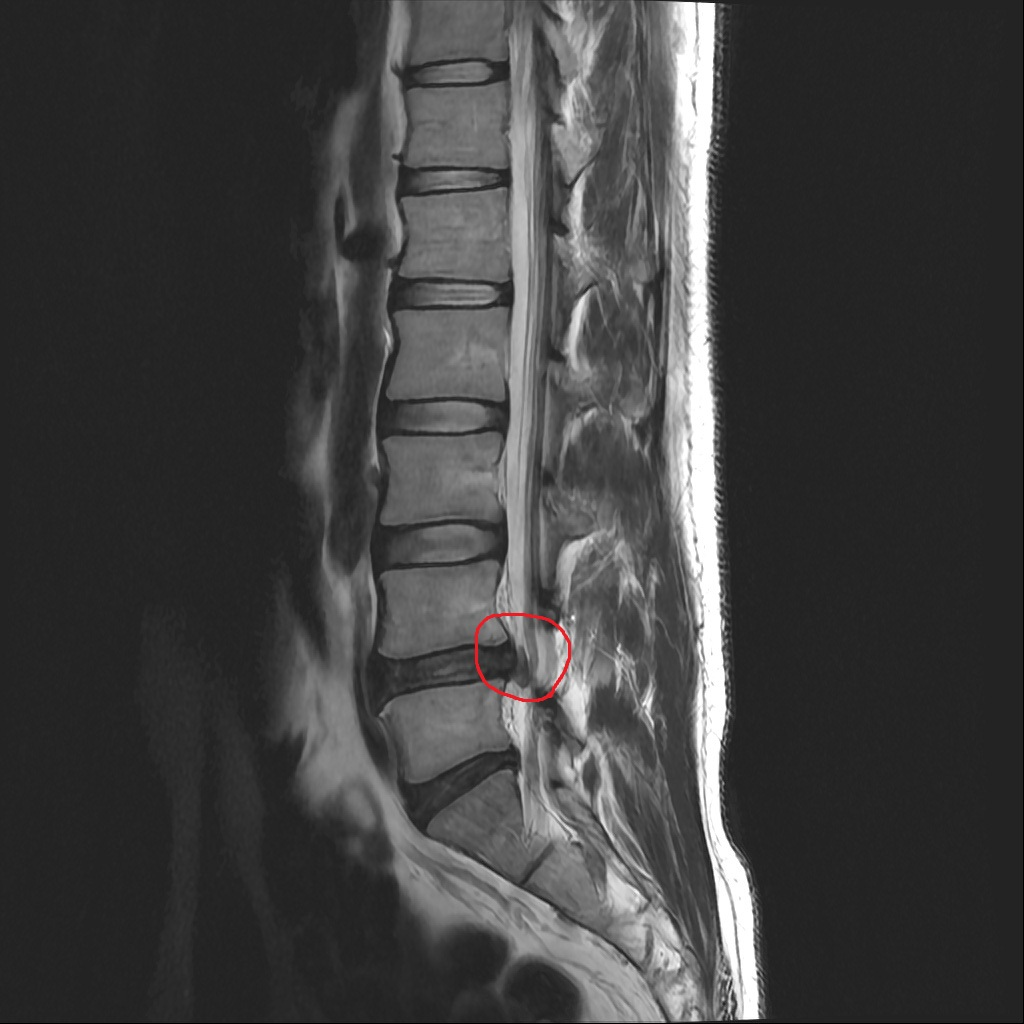

현재 4-5번 디스크 파열됬다고 들었구요, 왼쪽 발가락 안움직임과 발목안올라감(풋드랍) 있습니다. 침근전도검사에서 탈신경 과 신경근병증 결과가나온상태입니다. 터진부위 사진 2장에 신경눌림이 뚜렷하게 보이는건지 어떤게 신경인지 궁금합니다.

수핵의 탈출, 신경의 눌림이 저명하게 관찰되고 있습니다. 붉은 색으로 표시하신 부분에 해당합니다.